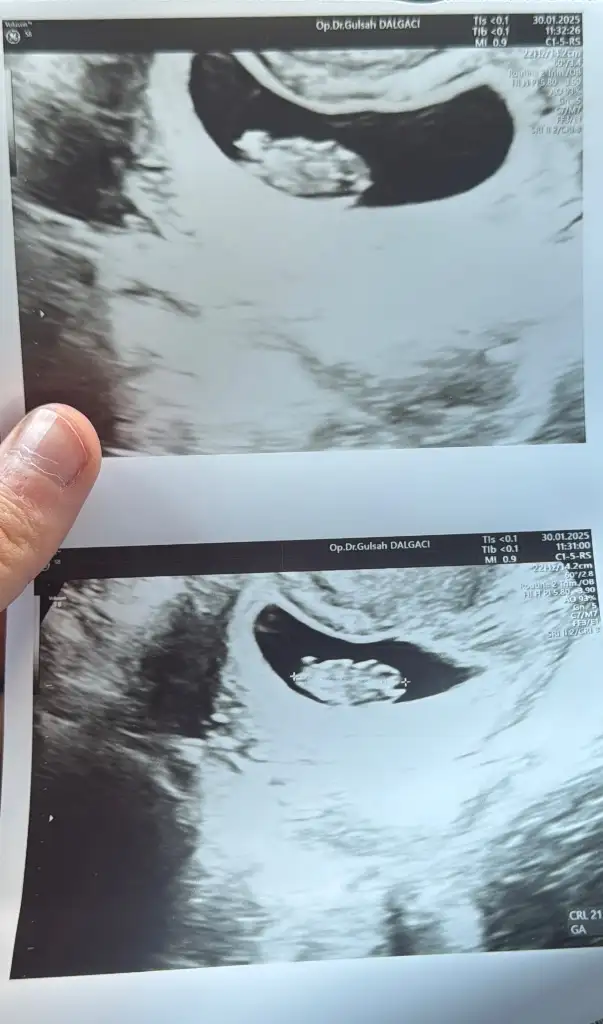

Anlayan birinden yorum lütfen

Kizlar bende az çok ramziden anlıyorum ama bu ultrason farklı geldi ultrason terimleri sol tarafta kalınca bebekte sagdamidir soldamidir çözemedim anlayan varsa cinsiyet tahmininde bulunabilirmi M meryem2132 Rica etsem sende bakarmisin kafam karıştı da benim